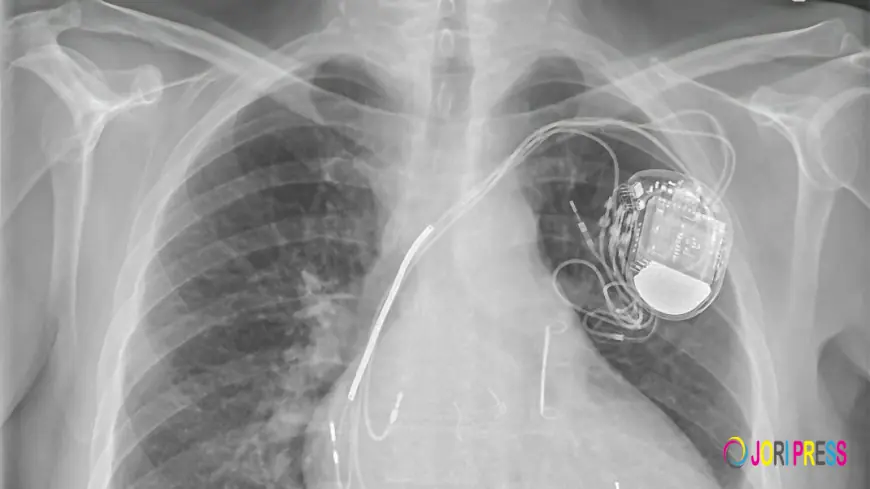

This demographic shift creates sustained demand for diagnostic and therapeutic devices. Hospitals and cardiac centers require advanced tools such as implantable pacemakers, catheter ablation systems, and cardiac monitoring devices to manage the increasing patient load effectively. The continuous influx of newly diagnosed patients ensures steady market demand.